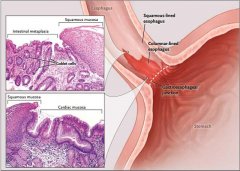

导语 食管下段的鳞状上皮被柱状上皮覆盖,称Barrett食管,又称巴雷特食管。

导语 食管下段的鳞状上皮被柱状上皮覆盖,称Barrett食管,又称巴雷特食管。

导语 食管下段的鳞状上皮被柱状上皮覆盖,称Barrett食管,又称巴雷特食管。

导语 食管下段的鳞状上皮被柱状上皮覆盖,称Barrett食管,又称巴雷特食管。